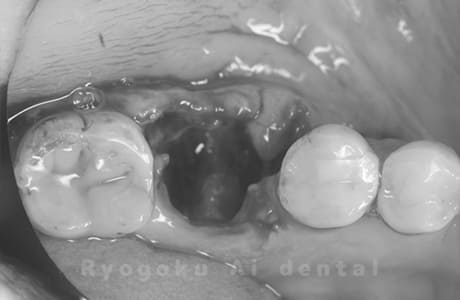

Case12

-

- 原因

- 左下7番歯牙破折

- 治療内容

- インプラント治療

- 治療費用

- 約600,000円

左下の奥歯が痛いとのことでご来院された患者様です。歯が完全に割れており、保存が不可能であったため、抜歯を行い、その際に骨に変わるお薬を入れ、十分な治癒を待ってからインプラント治療を行いました。経過良好で、大変満足されました。

<リスク・副作用>

治療後、痛みや違和感、出血、腫れなどが出る事があります。喫煙者、糖尿病などの方の場合、歯が生着しない場合があります。